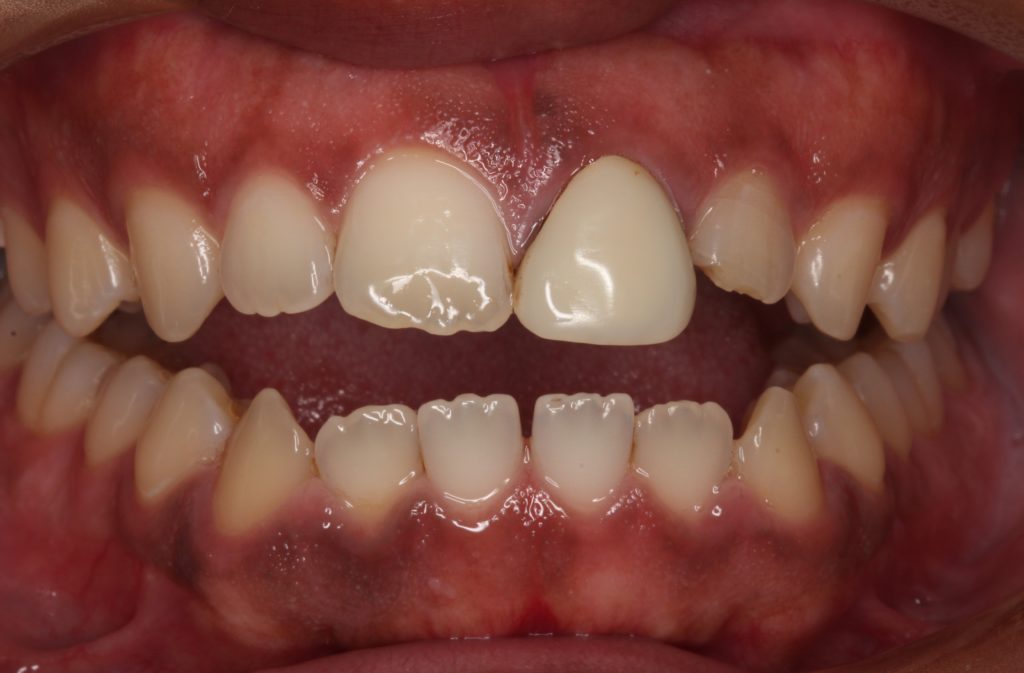

パッと見て前歯が1本浮いているのが分かります。

この歯ですね。

形も丸すぎていますし、色も白く、天然の歯のような透明感がありません。

このかぶせ物(クラウン)は保険の人工歯で、レジン前装冠というかぶせ物です。

表面の白く見えるのはレジンというプラスティックで、内部と裏側に金属が使われています。

レジンを使っているので透明感が無く、塗ったような単色の仕上がりで、経年劣化で変色をします。

今回の人工歯は色も形も全然合っていないものが入っています。